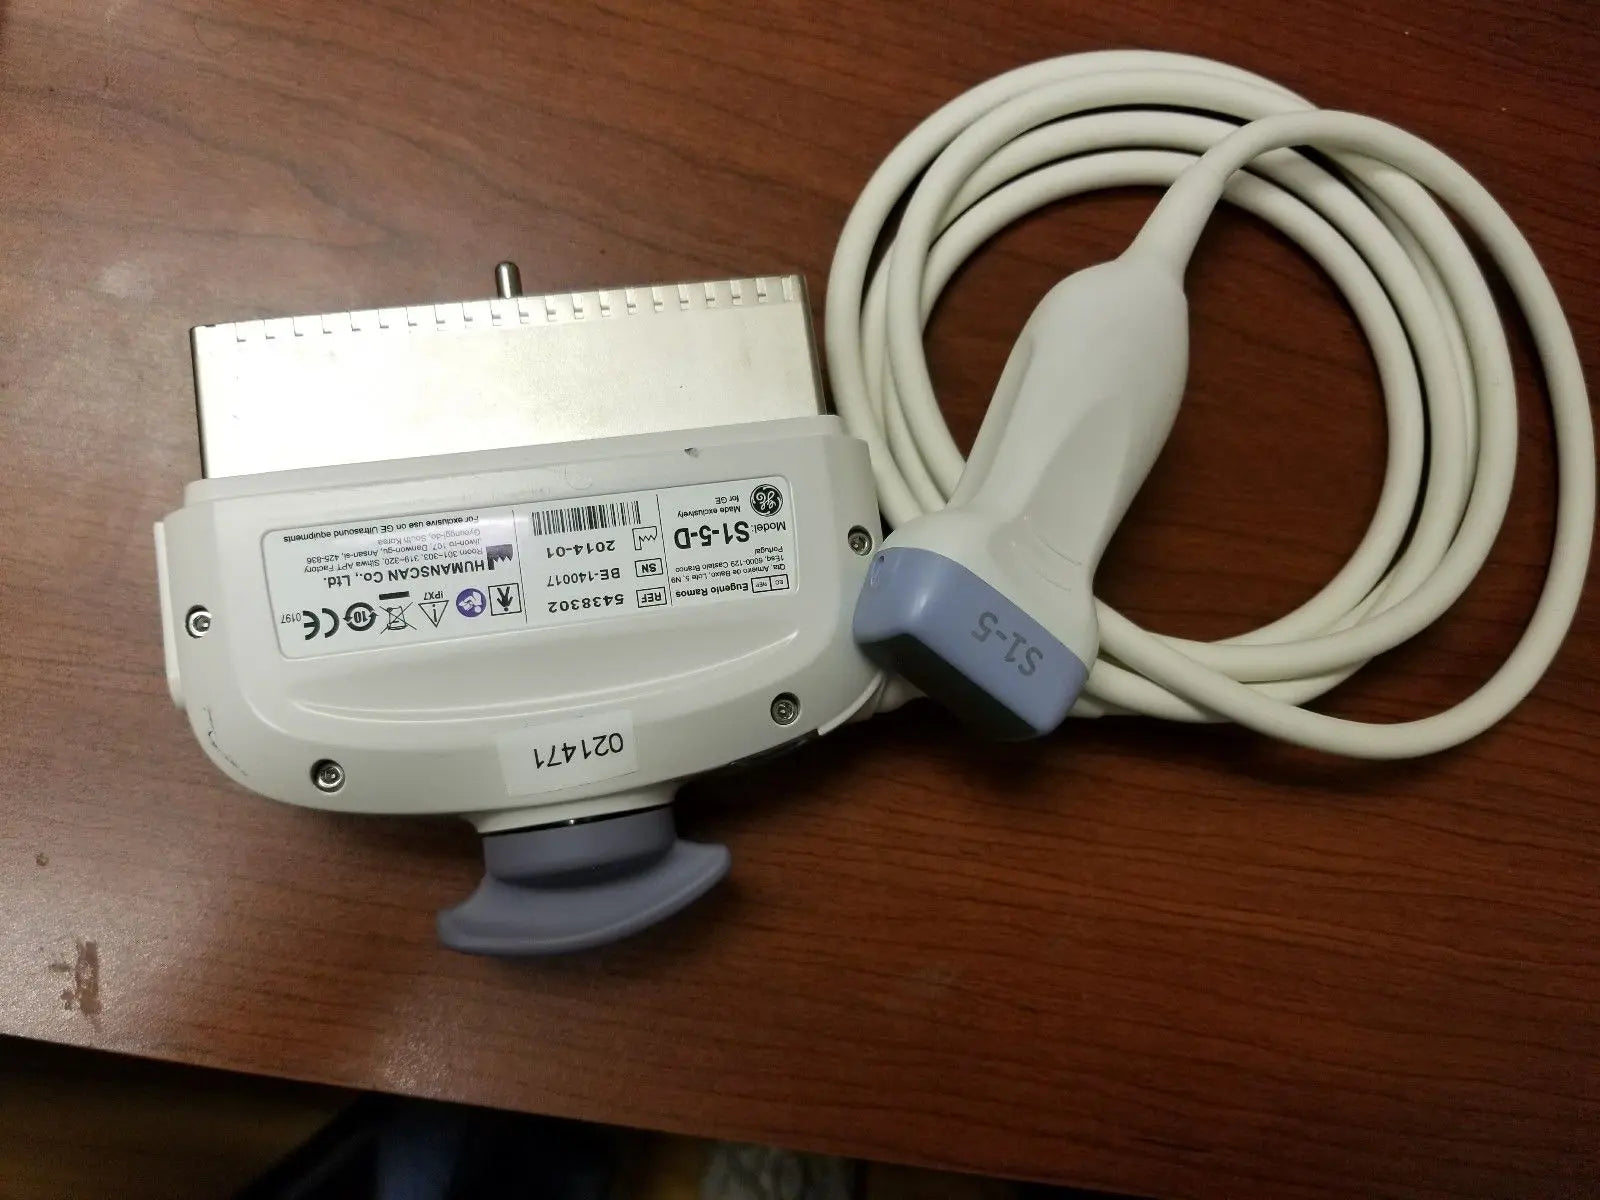

DIAGNOSTIC ULTRASOUND MACHINES FOR SALE

2017 GE IC9 -RS probe for GE Ultrasound

Sale price$ 8,395.14